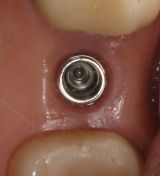

Si noti la perfetta integrazione dell'impianto a livello tissutale e la perfetta integrazione estetica del manufatto protesico.

L'uso di un impianto tissue level ha il grande vantaggio per i nostri pazienti di non dover subire un secondo rientro chirurgico. L'utilizzo è limitato ai casi da noi selezionati.